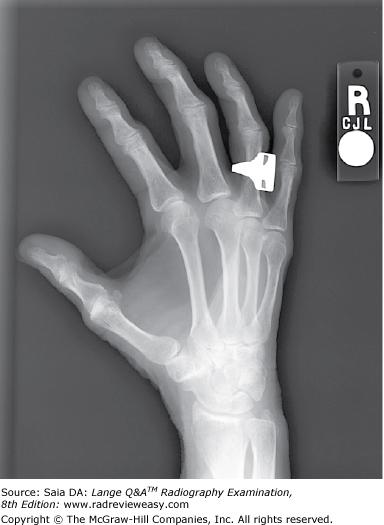

Which of the following statements regarding Figure 2–10 is (are) true?

- Correct degree of rotation is present.

- Midphalanges are foreshortened.

- Fingers are parallel to the IR

1 and 2 only